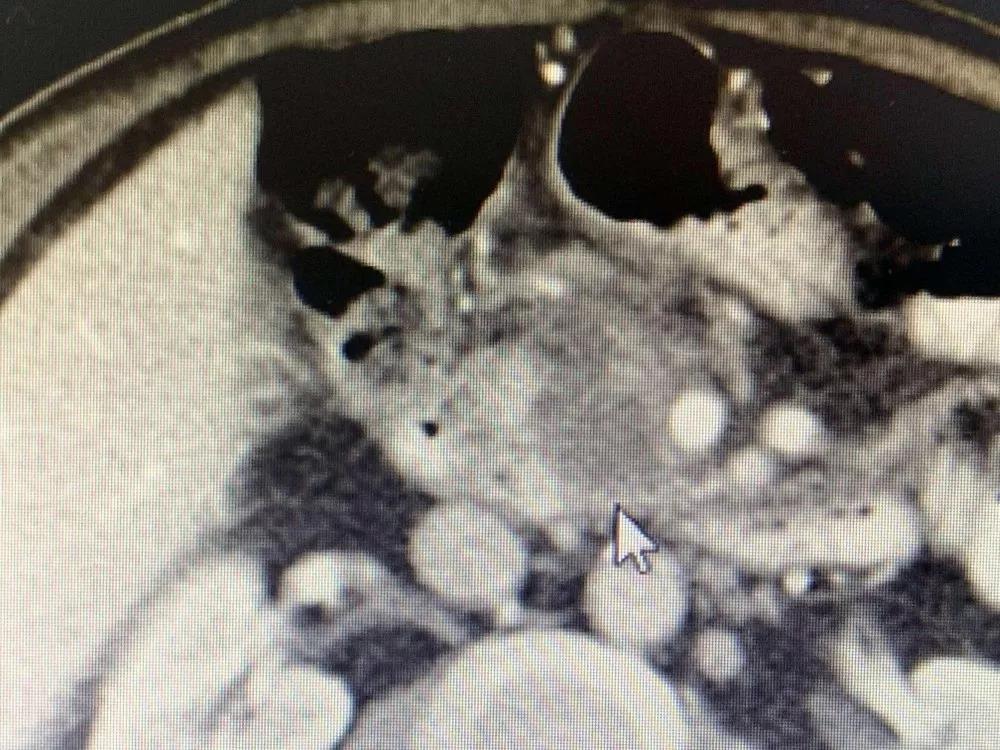

До операции опухоль поджелудочной железы окружает кровеносные сосуды и обнаруживаются метастазы в брюшных лимфатических узлах.

Медсестра сказала мне, что он и его семья были очень добрыми, и они улыбались и кивали вам, когда приветствовали. Было сказано, что он внезапно почувствовал боль в верхней части живота в апреле этого года. Позже в мае он прошел обследование в местной больнице. Неподтвержденная масса в поджелудочной железе размером 3 см была обнаружена вблизи верхней брыжеечной вены, которая предположительно была раком поджелудочной железы. 25 июля у него было еще одно обследование, и его состояние ухудшилось. Опухоль проникла в верхнюю брыжеечную вену и артерию; многочисленные маленькие лимфатические узлы были обнаружены перед полой веной и вблизи аорты. Из-за ограниченных медицинских ресурсов лучшего лечения в Непале не было. Затем его врач порекомендовал ему Онкологическую больницу Фуда.

Необратимая электропорация при опухоли поджелудочной железы

Для дальнейшего лечения как можно скорее его сын привез его в Онкологическую больницу Фуда 31 августа. После обследования ему был поставлен диагноз несоциализированная аденокарцинома III стадии в поджелудочной железе и диабет II типа с множественными узлами в печени, легких и щитовидной железе. После обсуждения с доктором Ню Личжи и медицинской командой он и его семья согласились провести катетеризацию в подключичной вене 6 сентября и на сдедующий день необратимую электропорацию при опухоли поджелудочной железы. После интенсивной терапии его состояние улучшалось с каждым днем.

Во время утреннего обхода доктор Ню и доктор Ли пришли в его палату. В то время он сидел в постели со скрещенными ногами и разговаривал со своей семьей. Когда он увидел приходящих врачей, он почувствовал себя счастливым. Доктор Ли сказал: «Через неделю после операции отчет КТ Ратана показал полный некроз опухоли, и онкомаркер СА199 вернулся к норме».